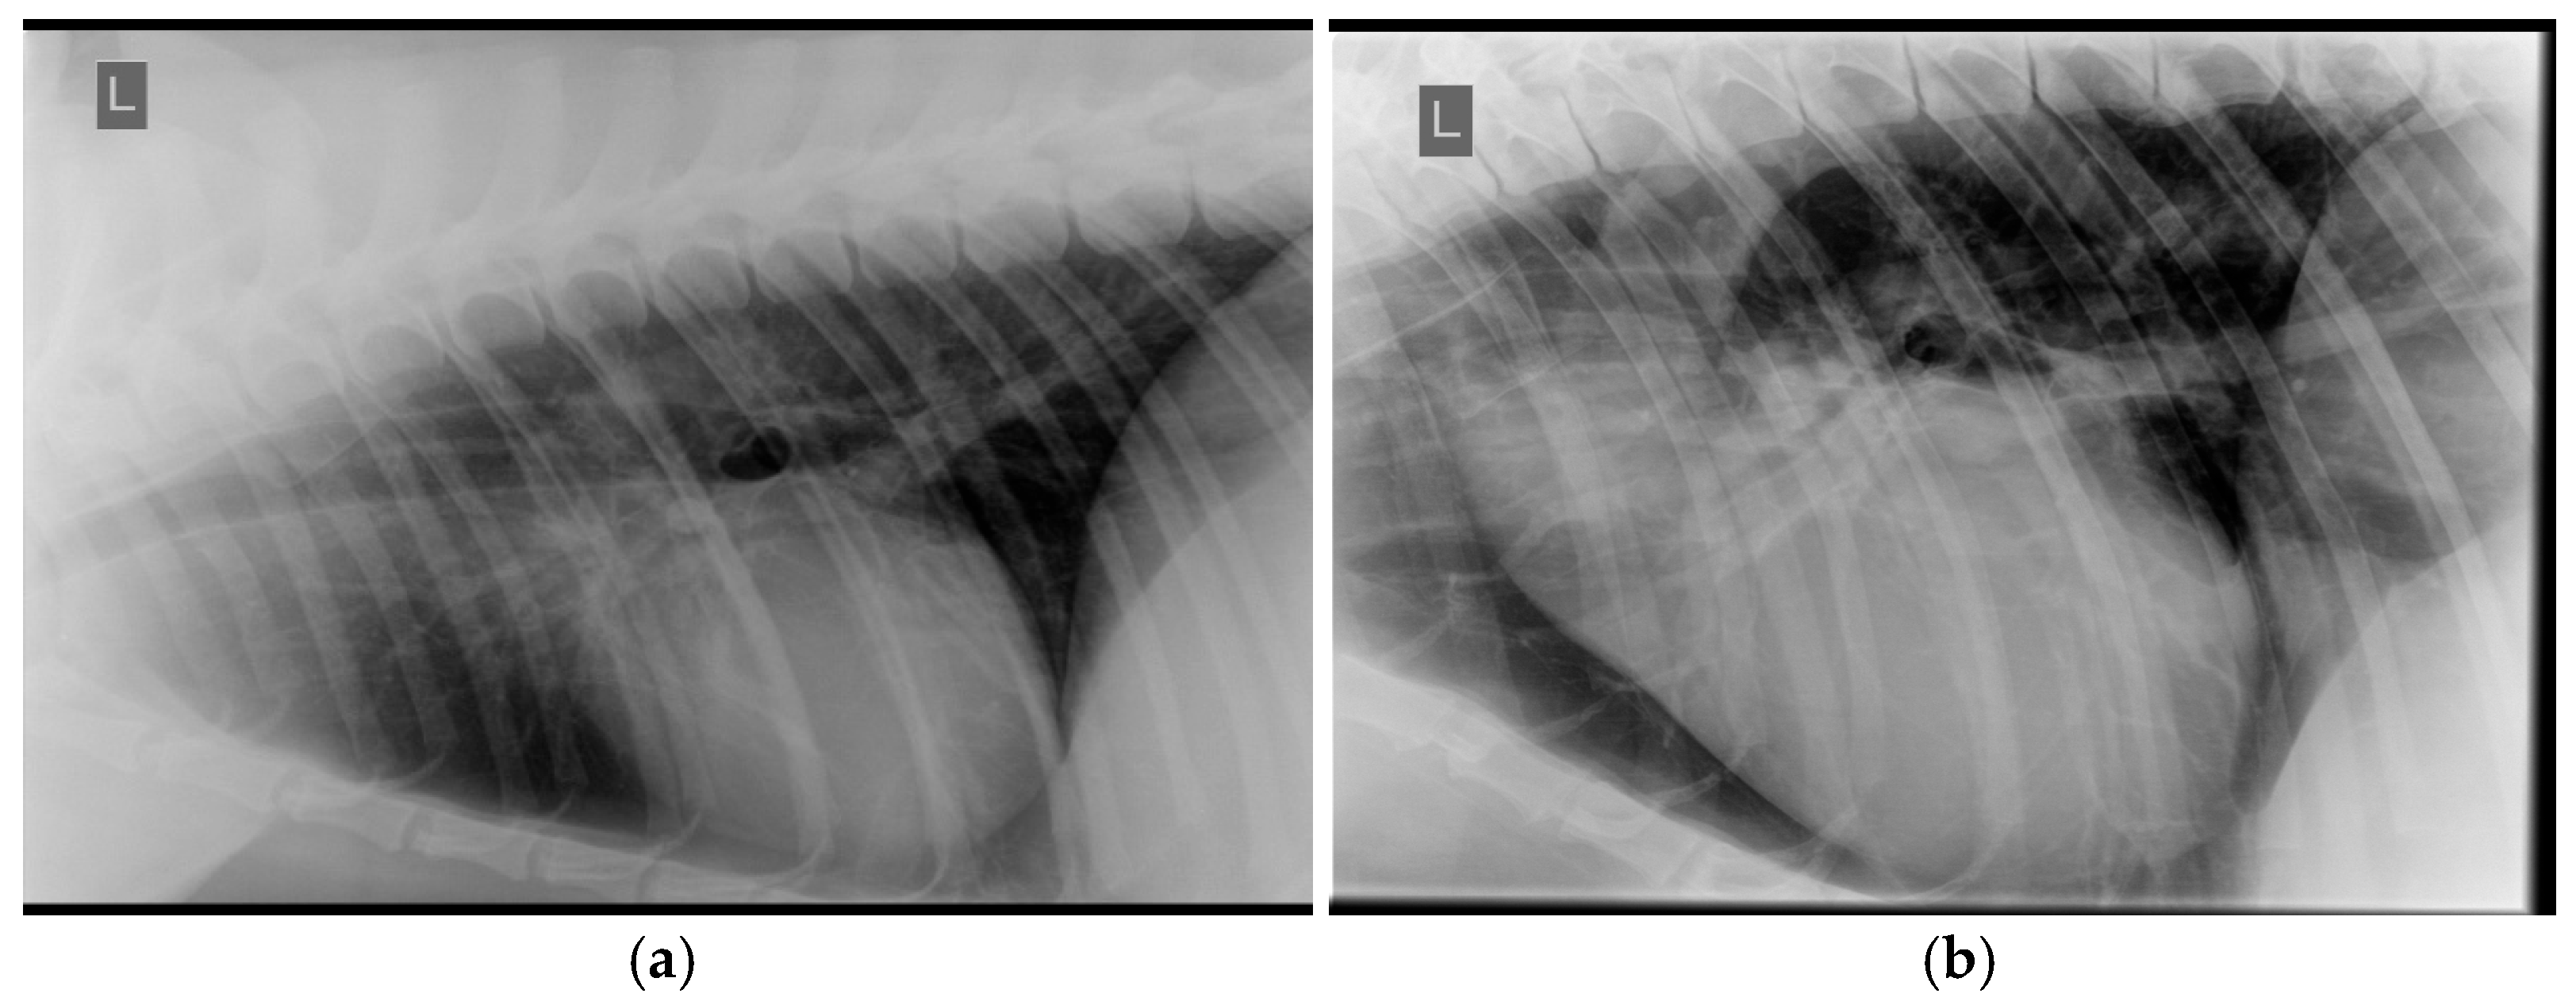

- Nelson, O.L.; Reidesel, E.; Ware, W.A.; Christensen, W.F. Echocardiographic and radiographic changes associated with systemic hypertension in cats. J. Vet. Intern. Med. 2002, 16, 418–425. [Google Scholar] [CrossRef]